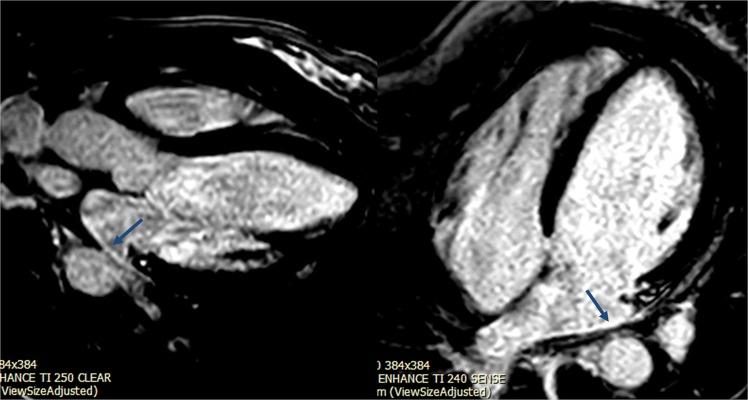

Increased extracellular volume (ECV) by CMR is a marker of interstitial myocardial fibrosis and is associated with diastolic dysfunction in sickle cell anemia (SCA). Left atrial (LA) dysfunction and stiffness contribute to the development of diastolic heart failure in other settings. We aimed to evaluate LA function and stiffness associations with ECV, tricuspid regurgitation jet velocity (TRV) and exercise abnormalities in SCA. In a prospective study, individuals with SCA underwent CMR, echocardiography and exercise test. ECV was measured using MOLLI sequence. Atrial strain was studied in the 4- and 2-chamber views. LA stiffness was calculated as the ratio of echocardiographic E/e'-to-LA reservoir strain. Twenty-four participants with SCA were included (median age 20 years). ECV was increased in participant with SCA compared to our lab normal values (mean 0.44 ± 0.08 vs 0.26 ± 0.02, P < 0.0001). Six (25%) had LA LGE. ECV positively correlated with LA stiffness (r = 0.45, p = 0.04). There was a negative correlation between LA stiffness and %predicted VO2 (r = -0.50, p = 0.04). LA stiffness was moderately associated with increased TRV (r = 0.55, p < 0.005). LA stiffness is associated with ECV, exercise impairment and increased TRV. This study sheds insights on the interaction between LA function, RV hypertension, and myocardial fibrosis in SCA.

CMR 测量的细胞外容积(ECV)增加是心肌间质纤维化的标志物,与镰状细胞贫血(SCA)患者的舒张功能障碍相关。左心房(LA)功能障碍和僵硬会导致其他情况下舒张性心力衰竭的发展。我们旨在评估 LA 功能和僵硬与 ECV、三尖瓣反流射流速度(TRV)和 SCA 中的运动异常的关系。在一项前瞻性研究中,SCA 患者接受了 CMR、超声心动图和运动试验检查。使用 MOLLI 序列测量 ECV。在 4 腔和 2 腔视图中研究心房应变。LA 僵硬通过超声心动图 E/e'-与 LA 储备应变的比值计算得出。共纳入 24 名 SCA 患者(中位年龄 20 岁)。与本实验室的正常值相比,SCA 患者的 ECV 增加(均值 0.44±0.08 比 0.26±0.02,P<0.0001)。6 名(25%)患者有 LA LGE。ECV 与 LA 僵硬呈正相关(r=0.45,p=0.04)。LA 僵硬与预测 VO2%之间呈负相关(r=-0.50,p=0.04)。LA 僵硬与增加的 TRV 中度相关(r=0.55,p<0.005)。LA 僵硬与 ECV、运动功能障碍和增加的 TRV 相关。这项研究深入了解了 SCA 中 LA 功能、RV 高血压和心肌纤维化之间的相互作用。